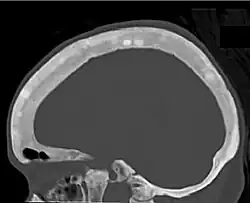

Ground glass density of the skull.[18] -